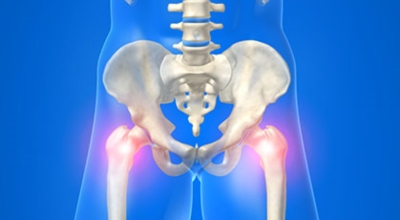

2. 고관절 통증 증상 - 보행이 어려워지고 보행시 절뚝거리는 증상

보통 고관절은 중장년층에게 생기는 증상으로 잘 알려져 있지만 최근 통계에 근거하면 젊은 층의 환자들의 비중도 늘어가고 있다고 하네요.

각별히 젊은 남성분들에게 잘 발생하며 엉덩이와 골반 주위에 뻐근한 통증이 동반되며 정상적인 보행이 되지 않고 절뚝거리는 증상이 나타난다면 대퇴골두 무혈성 괴사일 가능성이 있습니다. 이 증상은 괴사 부위의 골절이 발생되어 고관절 훼손으로 이어지면 생기는 증상으로 아직까지 정확한 원인은 규명하기 힘드나 과음이나 고지혈증, 스테로이드 과남용이 영향을 줄 수 있답니다.